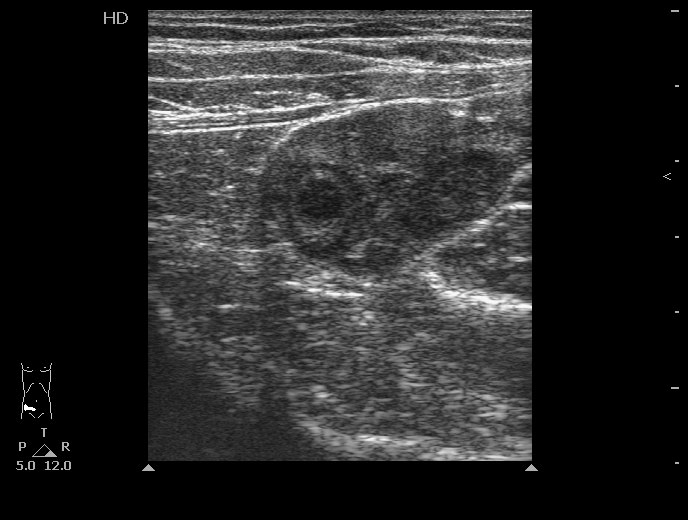

УЗИ:просто правый яичник у беременной

Беременная, боли в правой подвздошной области.

В правой подвздошной области лоцируется неоднородное образование включающее в себя структуру в виде "мишени" Закл: Эхо картина может соответствовать аппендикулярному инфильтрату

Похоже там аппендикс "узлом" завязан. ЗАКЛ: О.гангренозный аппендицит(деструктивный?). Периаппендикулярный абсцесс. Местный перитонит.

Да нет похоже это плодное яйцо...Надо гинекологию почитать..

Serg писал(а):Да нет похоже это плодное яйцо...Надо гинекологию почитать..

Беременность больших сроков.